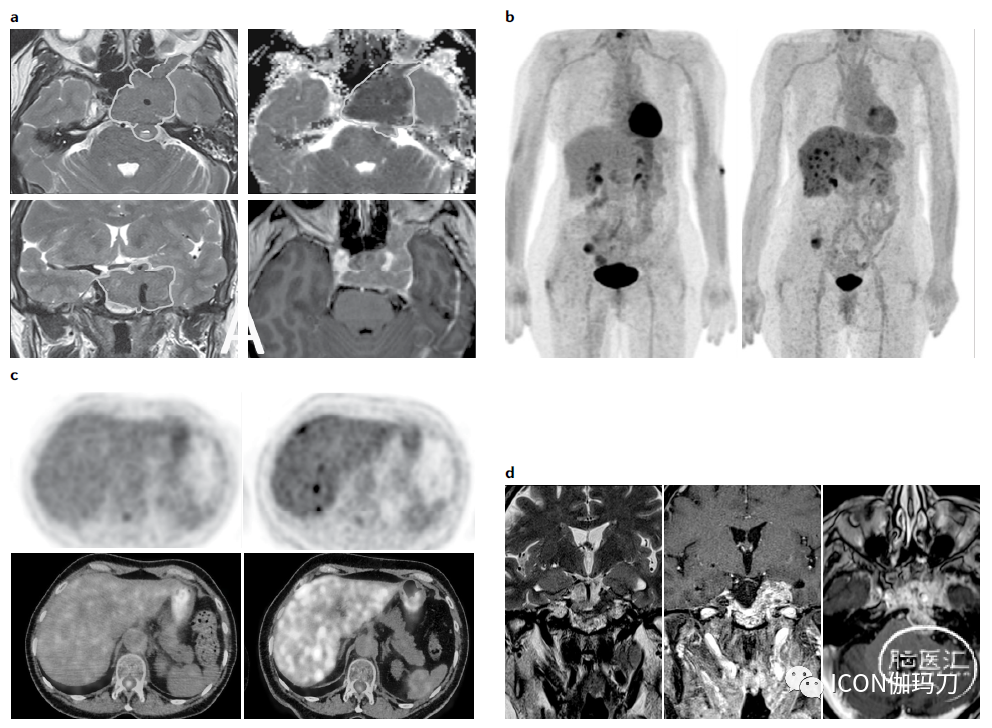

图3.泌乳素垂体癌的异常病程,在最初诊断到发现转移之间短期内(框1,患者2)。

a.诊断时的T2加权轴位垂体MRI图像(左上),诊断时T2加权冠状位垂体MRI图像(左下),右上为诊断时的垂体轴位表观扩散系数(ADC)加权MRI图像,右下为诊断时的垂体轴位T1加权钆剂增强MRI图像。起源于鞍区的肿瘤用白色标出,表明肿瘤向左侧海绵窦和左侧眶后区大块鞍外延伸。

b.初步扩展检查时全身18F-氟脱氧葡萄糖(18F-FDG) PET图像(左图;显示无远处转移)4个月后(右图;可见多个肝脏摄取部位)。

c.校正衰减轴位18F-FDG PET肝脏图像(左上)显示未见转移,4个月后(右上)显示病灶吸收的多发性转移。初始扩展检查中的轴位18F-FDG PET/CT融合肝脏图像(左下角;正常)和4个月后(右下;多发性转移灶表现为病灶吸收)。

d.初步扩展检查4个月后T2冠状位磁共振成像图(左图),T1冠状位磁共振成像增强图(中图)和T1轴位磁共振成像增强图(右图)显示垂体肿瘤稳定。